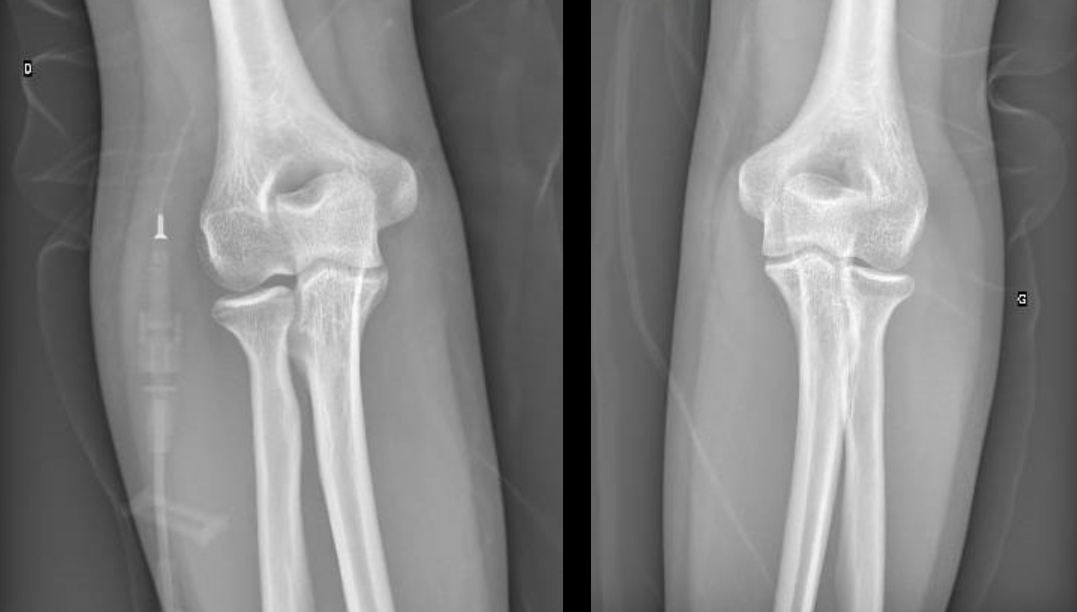

Vous la revoyez quatre mois après la fin de l’antibiothérapie avec des radiographies de contrôle (fig. 3 et 4).

Figure 3 (Source Salomé Abdellaoui, La Revue du Praticien)

Figure 4 (Source Salomé Abdellaoui, La Revue du Praticien)

On voit sur les radiographies que l’articulation est abîmée avec un pincement articulaire à gauche, il y a donc peu de chance que le flessum récupère totalement.

Il n’y pas de douleur ou de retentissement fonctionnel associé au flessum de coude donc pas d’indication actuelle à une prise en charge chirurgicale. En revanche, l’articulation va probablement évoluer vers une arthrose précoce et possiblement vers la mise en place d’une prothèse dans un second temps.